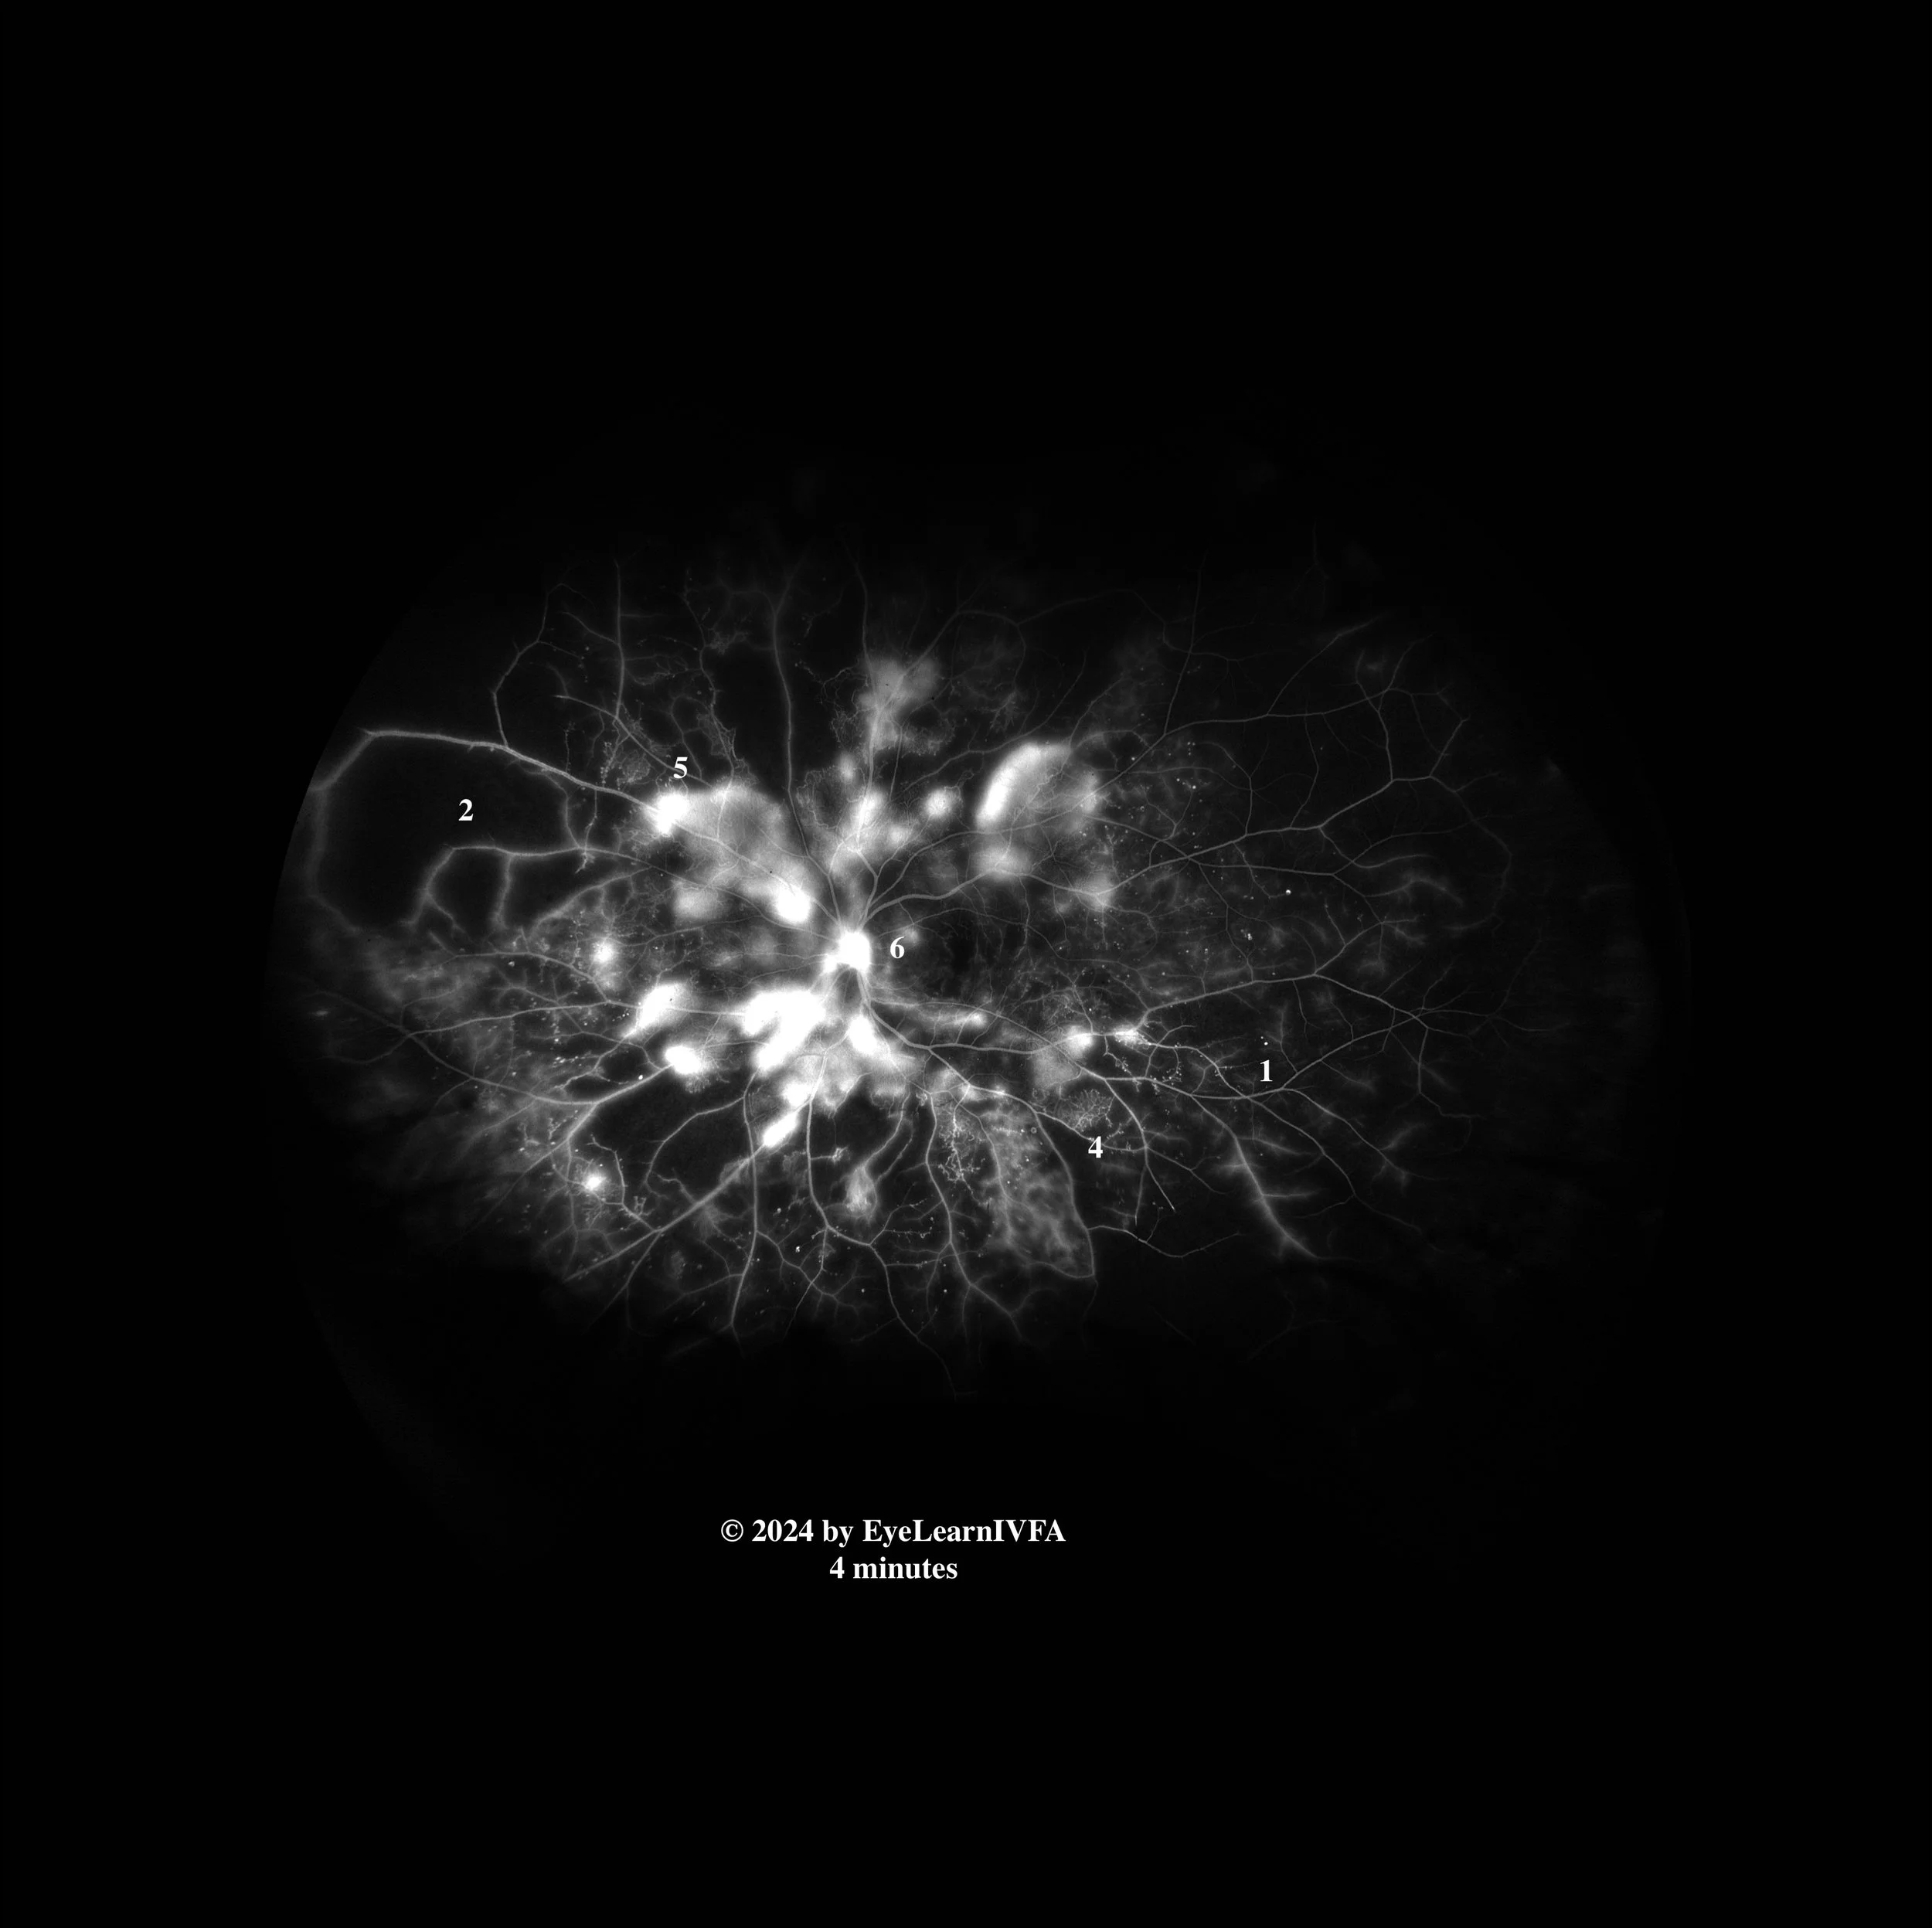

Phase:

Describe the pattern of abnormal fluorescence in bullet point form.

If multiple features are present, please insert small white numbers in numeric form label the corresponding description.

• Ex. Posterior pole and peripheral hypofluoresence from hypoperfusion secondary to capillary drop out (2)